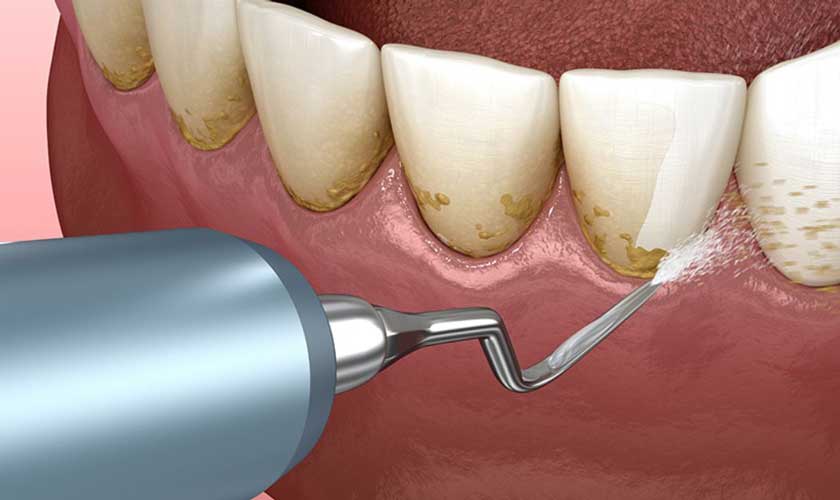

- Cạo vôi răng: Bác sĩ sử dụng máy cạo vôi răng siêu âm để loại bỏ mảng bám, vôi răng ra khỏi bề mặt răng và bên dưới nướu, từ đó giúp nướu phục hồi và giảm viêm.

- Đánh bóng răng: Vôi răng khi đã được loại bỏ, bác sĩ sẽ tiến hành đánh bóng răng để làm mịn bề mặt răng, hạn chế tình trạng vôi răng, mảng bám tích tụ. Điều này sẽ giúp thu hẹp khoảng cách giữa mô nướu và bề mặt răng, từ đó giảm kích thước túi.

Cạo vôi răng để khôi phục sức khỏe của nướu